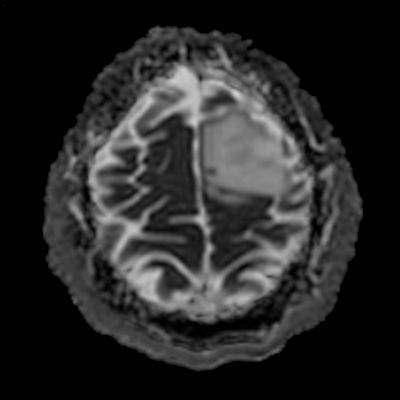

- ADC görüntülerde lezyonda sinyal artışları ile karakterize difüzyon artışı (ok) izleniyor. Bu alana yönelik yapılan multivoksel MR spektroskopi incelemesinde (ok) kolin pikinde artış ve NAA pikinde azalma izleniyor. Cho/Cr oranı 1.76 ölçülüyor.

- DAG’de düşük ADC değerleri varsa bu daha yüksek mitotik aktiviteyi gösterebilir (grade 3–4).

- MR spektroskopide tipik olarak yüksek kolin piki, düşük NAA piki, yüksek kolin/kreatin oranı görülür.

- Miyo-inositol / kreatin oranında artış görülebilir.